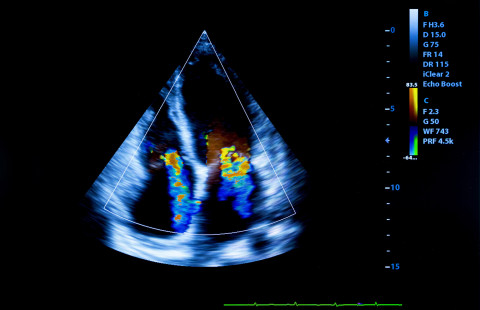

The doctoral research of Haitham Ballo, MBChB, focuses on advanced imaging techniques of coronary arteries, myocardial function, and ischemia.